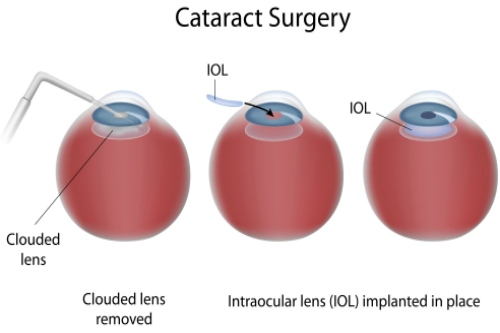

家人们,我做白内障三焦晶体植入手术已经有一段时间啦,现在来给大家好好分享下我1个月和6个月的真实感受,真的就像告别了“毛玻璃”国内外,重见清晰光明!

我都忍不住感叹,这三焦晶体植入手术简直就是我的救星,让我重新找回了清晰的视野。

家人们,如果你们也被白内障困扰,不妨考虑考虑三焦晶体植入手术。相信我,就像我一样,告别“毛玻璃”国内外,开启清晰、多彩的新生活!